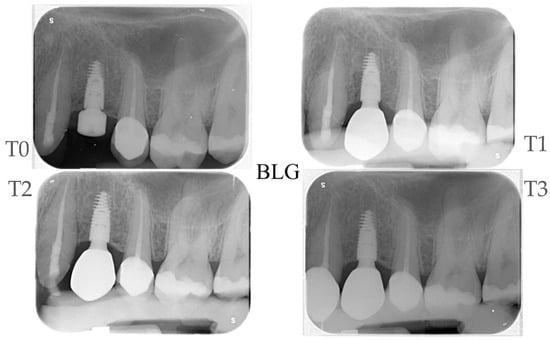

2.4. Radiographic Evaluations